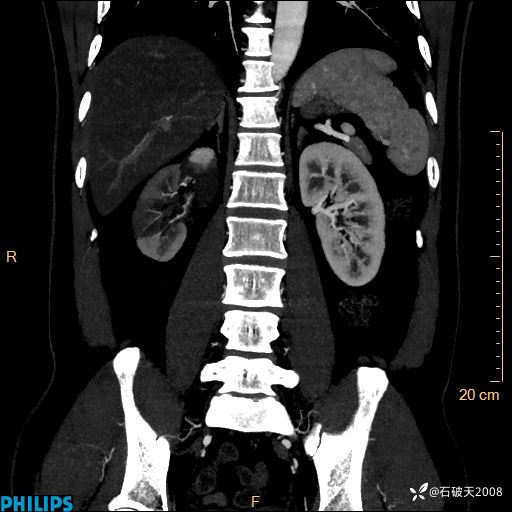

冠状位

MIP